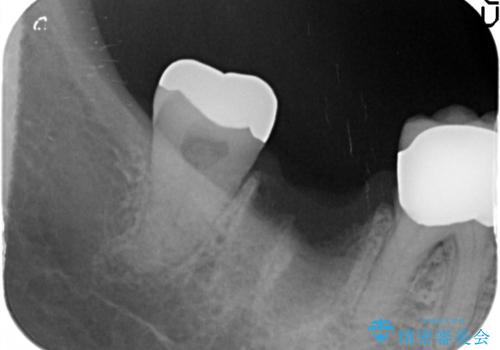

- 右下の歯を抜いた箇所に親知らずを矯正治療で移動できないかというご相談で来院。

親知らずを一本分前には基本的には難しいという説明をしました。

また、受け口のかみ合わせのため、下の親知らずは上の7番目の歯に咬合して機能しているため、そのままの位置の方が良さそうでした。

欠損の部分にはブリッジまたはインプラント、義歯の選択肢がありますが、インプラント治療をご希望されました。

他院で抜歯後いらしたため、骨ができるのを待って、オペは2回法で行っております。